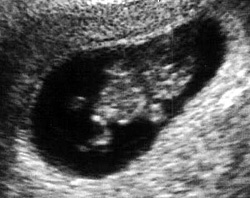

الأسبوع التاسع:

ينتقل الآن مولدك في المستقبل إلي مرحلة مختلفة في النمو حيث يختلف اسمه الآن وينتقل من مجرد حميل إلي جنين كما يسمى في الأغلب. يبدأ الرحم في الاتساع ليشتمل علي منطقة أوسع وأكبر، وينمو الجنين أكثر ويصبح حوالي 2.5 سم طولاً . تحدث تغيرات كثيرة للجنين من عضلات وأعصاب للقيام بوظائفها، تبدأ اليد في التثبت بالمعصم وتبدأ الجفون في تغطية منطقة العين. تظهر أيضاً مع بداية هذا الأسبوع تغيرات جسمانية علي السيدة كالتي تظهر في بداية الحمل حيث يتضخم الثدي بشكل أكبر ويتسع محيط الخصر.